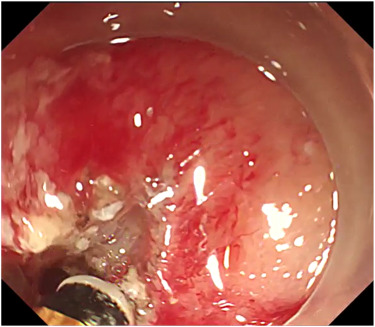

Matthew Eganhouse, MD, et al present a case of successful endoscopic therapy for bleeding in a walled-off necrosis cavity using through-the-scope clips, thermal therapy, and fibrin gel matrix. https://t.co/vmL7u5fP9K

#GITwitter